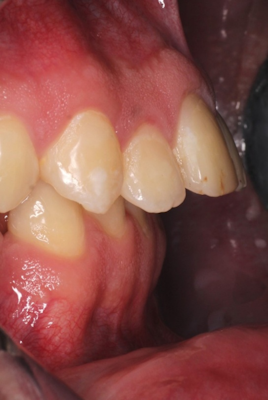

Caso de apiñamiento y sobremordida

Paciente pediátrico, masculino de 9 años de edad, acude acompañado de sus padres debido a la mala alineación de los dientes, y encías inflamadas (gingivitis). Buscan mejorar tanto la estética como la salud bucal desde una etapa temprana.

El paciente en su consulta de diagnóstico

Durante la valoración clínica se identificaron los siguientes hallazgos:

- Apiñamiento dental moderado en ambas arcadas

- Falta espacio para la erupción correcta de caninos superiores

- Sobremordida aumentada

- Encías inflamadas con enrojecimiento generalizado (gingivitis)

- Dentición mixta (presencia de dientes temporales y permanentes)